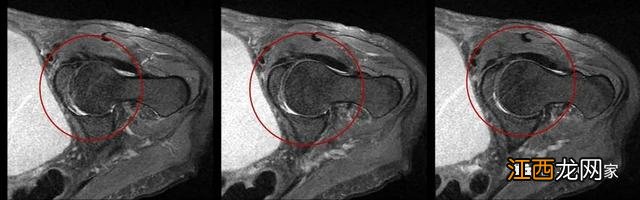

在髋关节x的扫描时,应排空尿液,特别是在进行单侧髋关节扫描时,上图,膀胱过度充盈对图像造成的影响 。